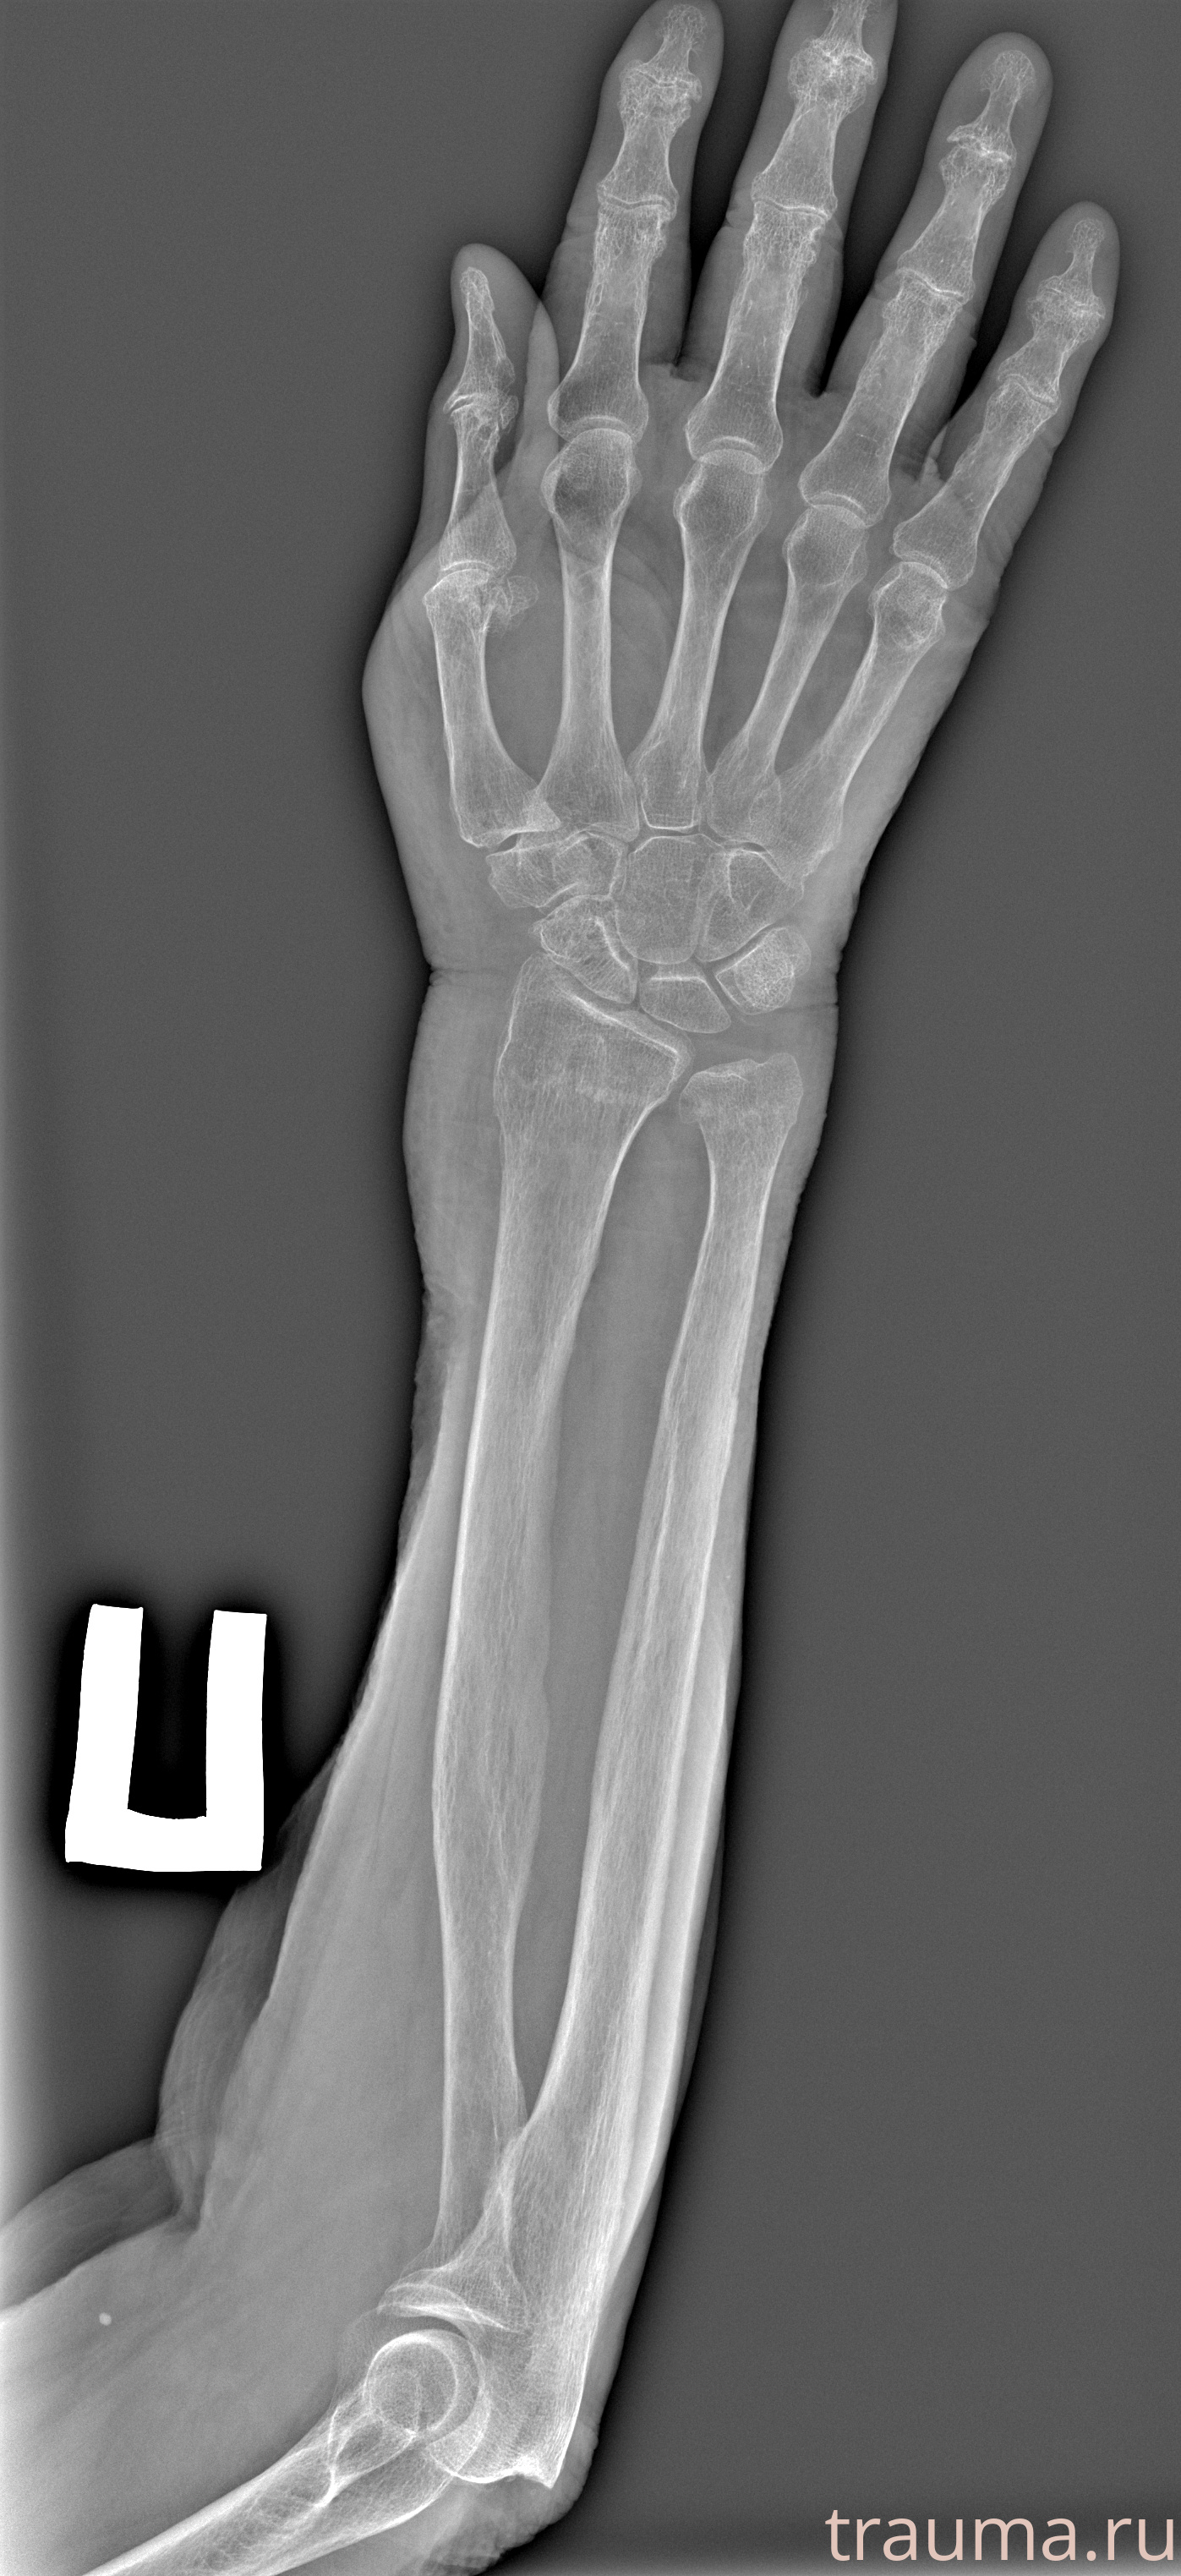

Перелом 3-5 ребер слева